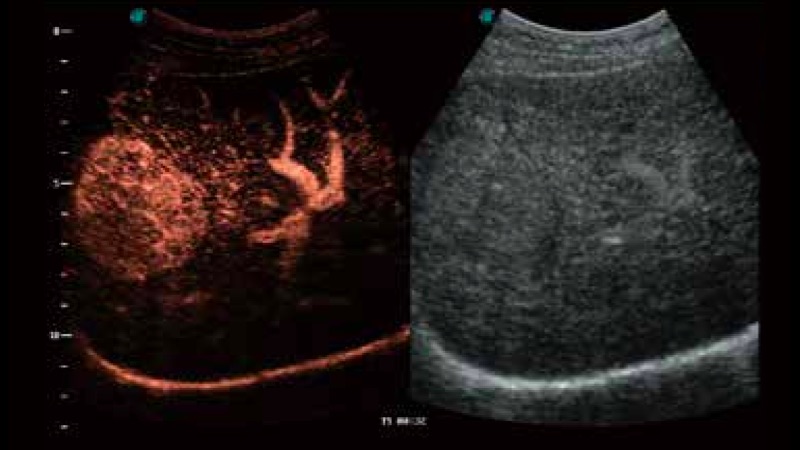

开立医疗通过不断的技术创新,为大众的生命健康提供持续关爱。P12 Plus采用全新一代超声成像平台,新平台旨在将真实还原组织解剖结构作为首要目标。平台采用全新集成化硬件模块,搭载新一代芯片,系统性能得到大幅提升,为您的诊断提供了丰富的临床信息。优异的图像表现,丰富的探头配置,全面的应用功能,为您日常诊断提供了可靠的助手。

凭借开立医疗先进的成像技术和优异的探头技术提供的清晰的图像表现,您可以更自信地做出临床决策。